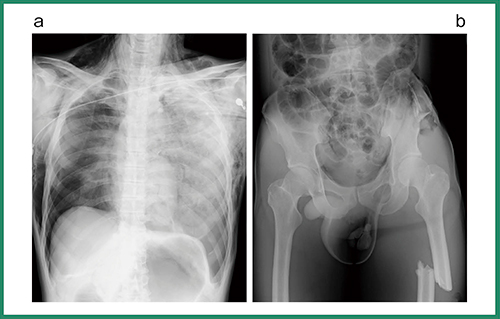

当センターでは,ホットライン入電後,ワイヤレス通信など装置の準備を行い待機する。Primary surveyでは胸部と骨盤の撮影を行うが,現場ではCALNEO flexの確認用PCの画面で,医師をはじめスタッフがその場で画像を参照することも多い。図6は,53歳,男性,転落外傷の患者の救急撮影だが,胸部はデフォルトでVG処理を適応し,骨盤部は通常の骨盤の処理と腹部のVG処理を行って,良い方の画像を転送している。Virtual Gridによって散乱線が効果的に除去されコントラストが改善し,実グリッド使用時よりも画質の向上を実感している。

図6 転落外傷で搬送された53歳,男性のVirtual Gridを用いたprimary survey画像

a:胸部 b:骨盤部